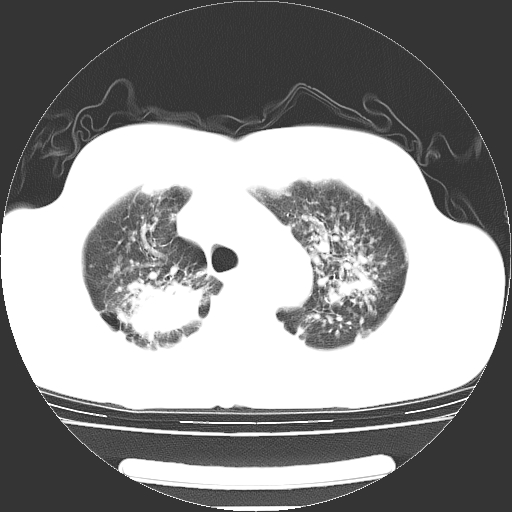

以下是引用yangyudong333在2008-4-29 5:38:00的发言:[br]比较典型的矽肺结节.支持[br]诊断依据:[br] 1.x线表现:[br] ①典型矽肺为多发直径 1~3mm 小结节,即矽结节,由胶原纤维和硅尘构成,可融合成团块,好发于上肺。[br] ②团块周围常有肺大泡。[br] ③胸内淋巴结增大、钙化。如肺门淋巴结呈蛋壳样钙化有助于与其他尘肺区别。[br] ④胸膜常广泛粘连、增厚。[br] 2.ct表现[br] ①两肺散在大小较为一致的小结节影,其密度较高,边界清楚。[br] ②小结节可融合为较大团块影,直径约 1cm ,甚至可达 10cm以上,易发生在上叶。[br] ③小结节周围常并有小叶中心气肿或弥漫性肺气肿。

以下是引用liuyue在2008-4-28 22:30:00的发言:[br]比较典型的矽肺结节.[br]请结合临床及化验除外矽肺合并肺结核之可能.